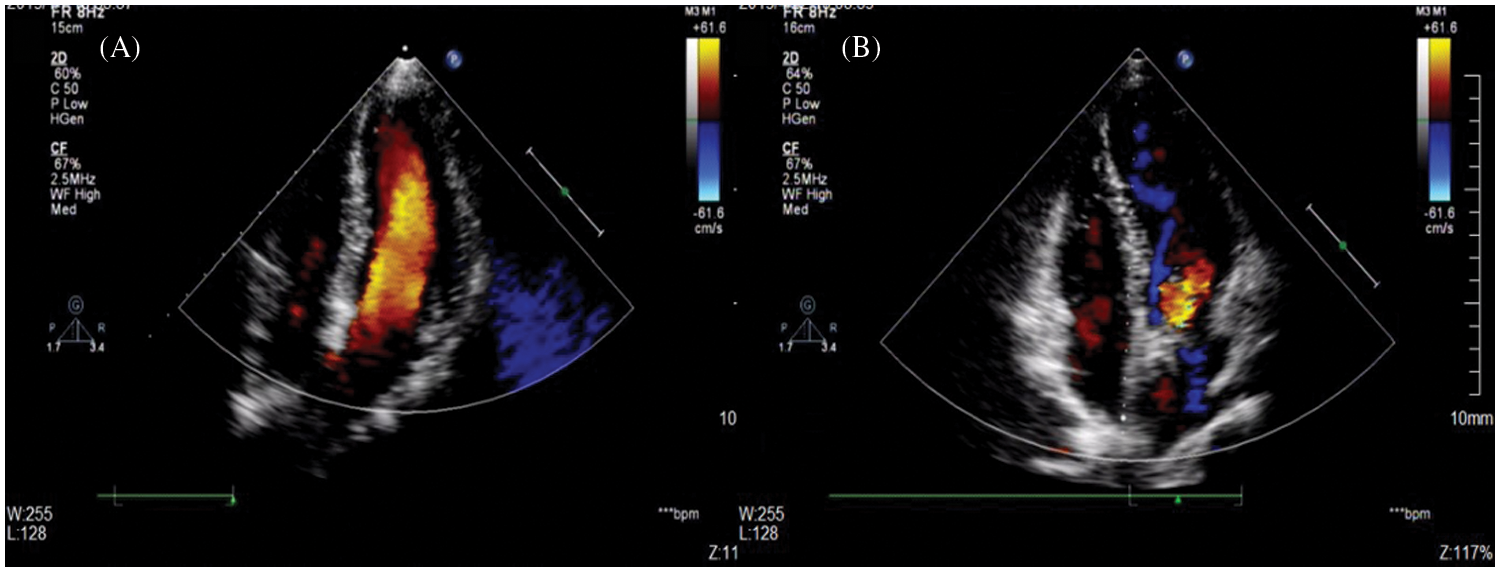

The major and minor adverse events are summarized in Table 3. A total of one major adverse event was noted. A 47-year-old female who had diabetes and a history of cerebral infarction suffered acute cerebral embolism 1 day after closure, was transferred to the neurology department, and was discharged on the 11th day after closure. Mild residual shunting after the procedure was the most common complication, with an overall rate of 44.6% as measured through TTE. The 83 cases of immediate residual shunt after closure were mild. There were 76 cases residual shunts between disks of the occluders, and 7 cases residual shunts around disks due to multiple outlets and anatomical morphology confirmed by TTE. However, these problems did not persist because most residual shunts diminished before each patient’s 12-month follow-up visit (Fig. 3). No patients developed either trivial or small residual shunt flow, as determined through echocardiography at the latest follow-up examination.

Figure 3: A mild residual shunt after the procedure did not persist. (A) TTE showed a postclosure mild residual shunt at the 1-month follow-up; (B) No residual shunt was found with TTE at the 12-month follow-up